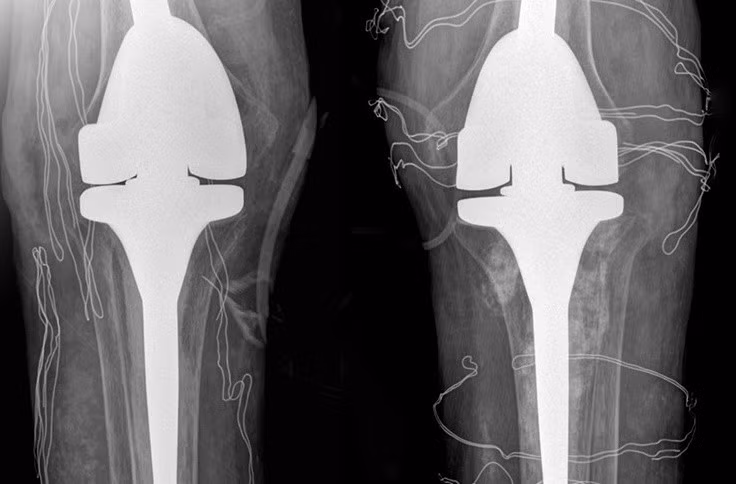

ThS.BS Nguyễn Quang Tôn Quyền, Phó khoa Chấn thương Chỉnh hình, Bệnh viện Đa khoa Tâm Anh Hà Nội chẩn đoán, bệnh nhân mất khả năng duỗi khớp gối, chỉ co được 60-70 độ, chụp X-quang cho thấy hai khớp gối bệnh nhân biến dạng nặng, tổn thương tophi khiến khớp và xương tiêu. Kiểm tra loại “thuốc” mua trên mạng mà anh T. uống, bác sĩ phát hiện là sản phẩm hỗ trợ sức khỏe đã bị Cục Quản lý Thực phẩm và Dược phẩm Mỹ (FDA) cảnh báo chứa chất dexamethasone gây nguy hiểm.

Phim chụp X-quang hai bên khớp gối nhân tạo của bệnh nhân. Ảnh: Bệnh viện Đa khoa Tâm Anh.

Nam bệnh nhân được chỉ định phẫu thuật thay khớp nhân tạo. Xét nghiệm máu trước mổ cho thấy nồng độ cortisol và ACTH (hormone kích thích tuyến thượng thận sản xuất cortisol) thấp. Bác sĩ Quyền chẩn đoán bệnh nhân bị suy tuyến thượng thận do lạm dụng chất dexamethasone dài ngày.

Ê-kíp bác sĩ loại bỏ các hạt tophi gây cản trở vận động, thay thế khớp gối đã tổn thương bằng loại khớp nhân tạo có bản lề, dành riêng cho bệnh nhân có các biến dạng khớp nghiêm trọng. Hậu phẫu, bệnh nhân tiếp tục truyền thuốc ổn định nồng độ hormone tuyến thượng thận trong 2 ngày, sau đó duy trì uống thuốc hormone thay thế.